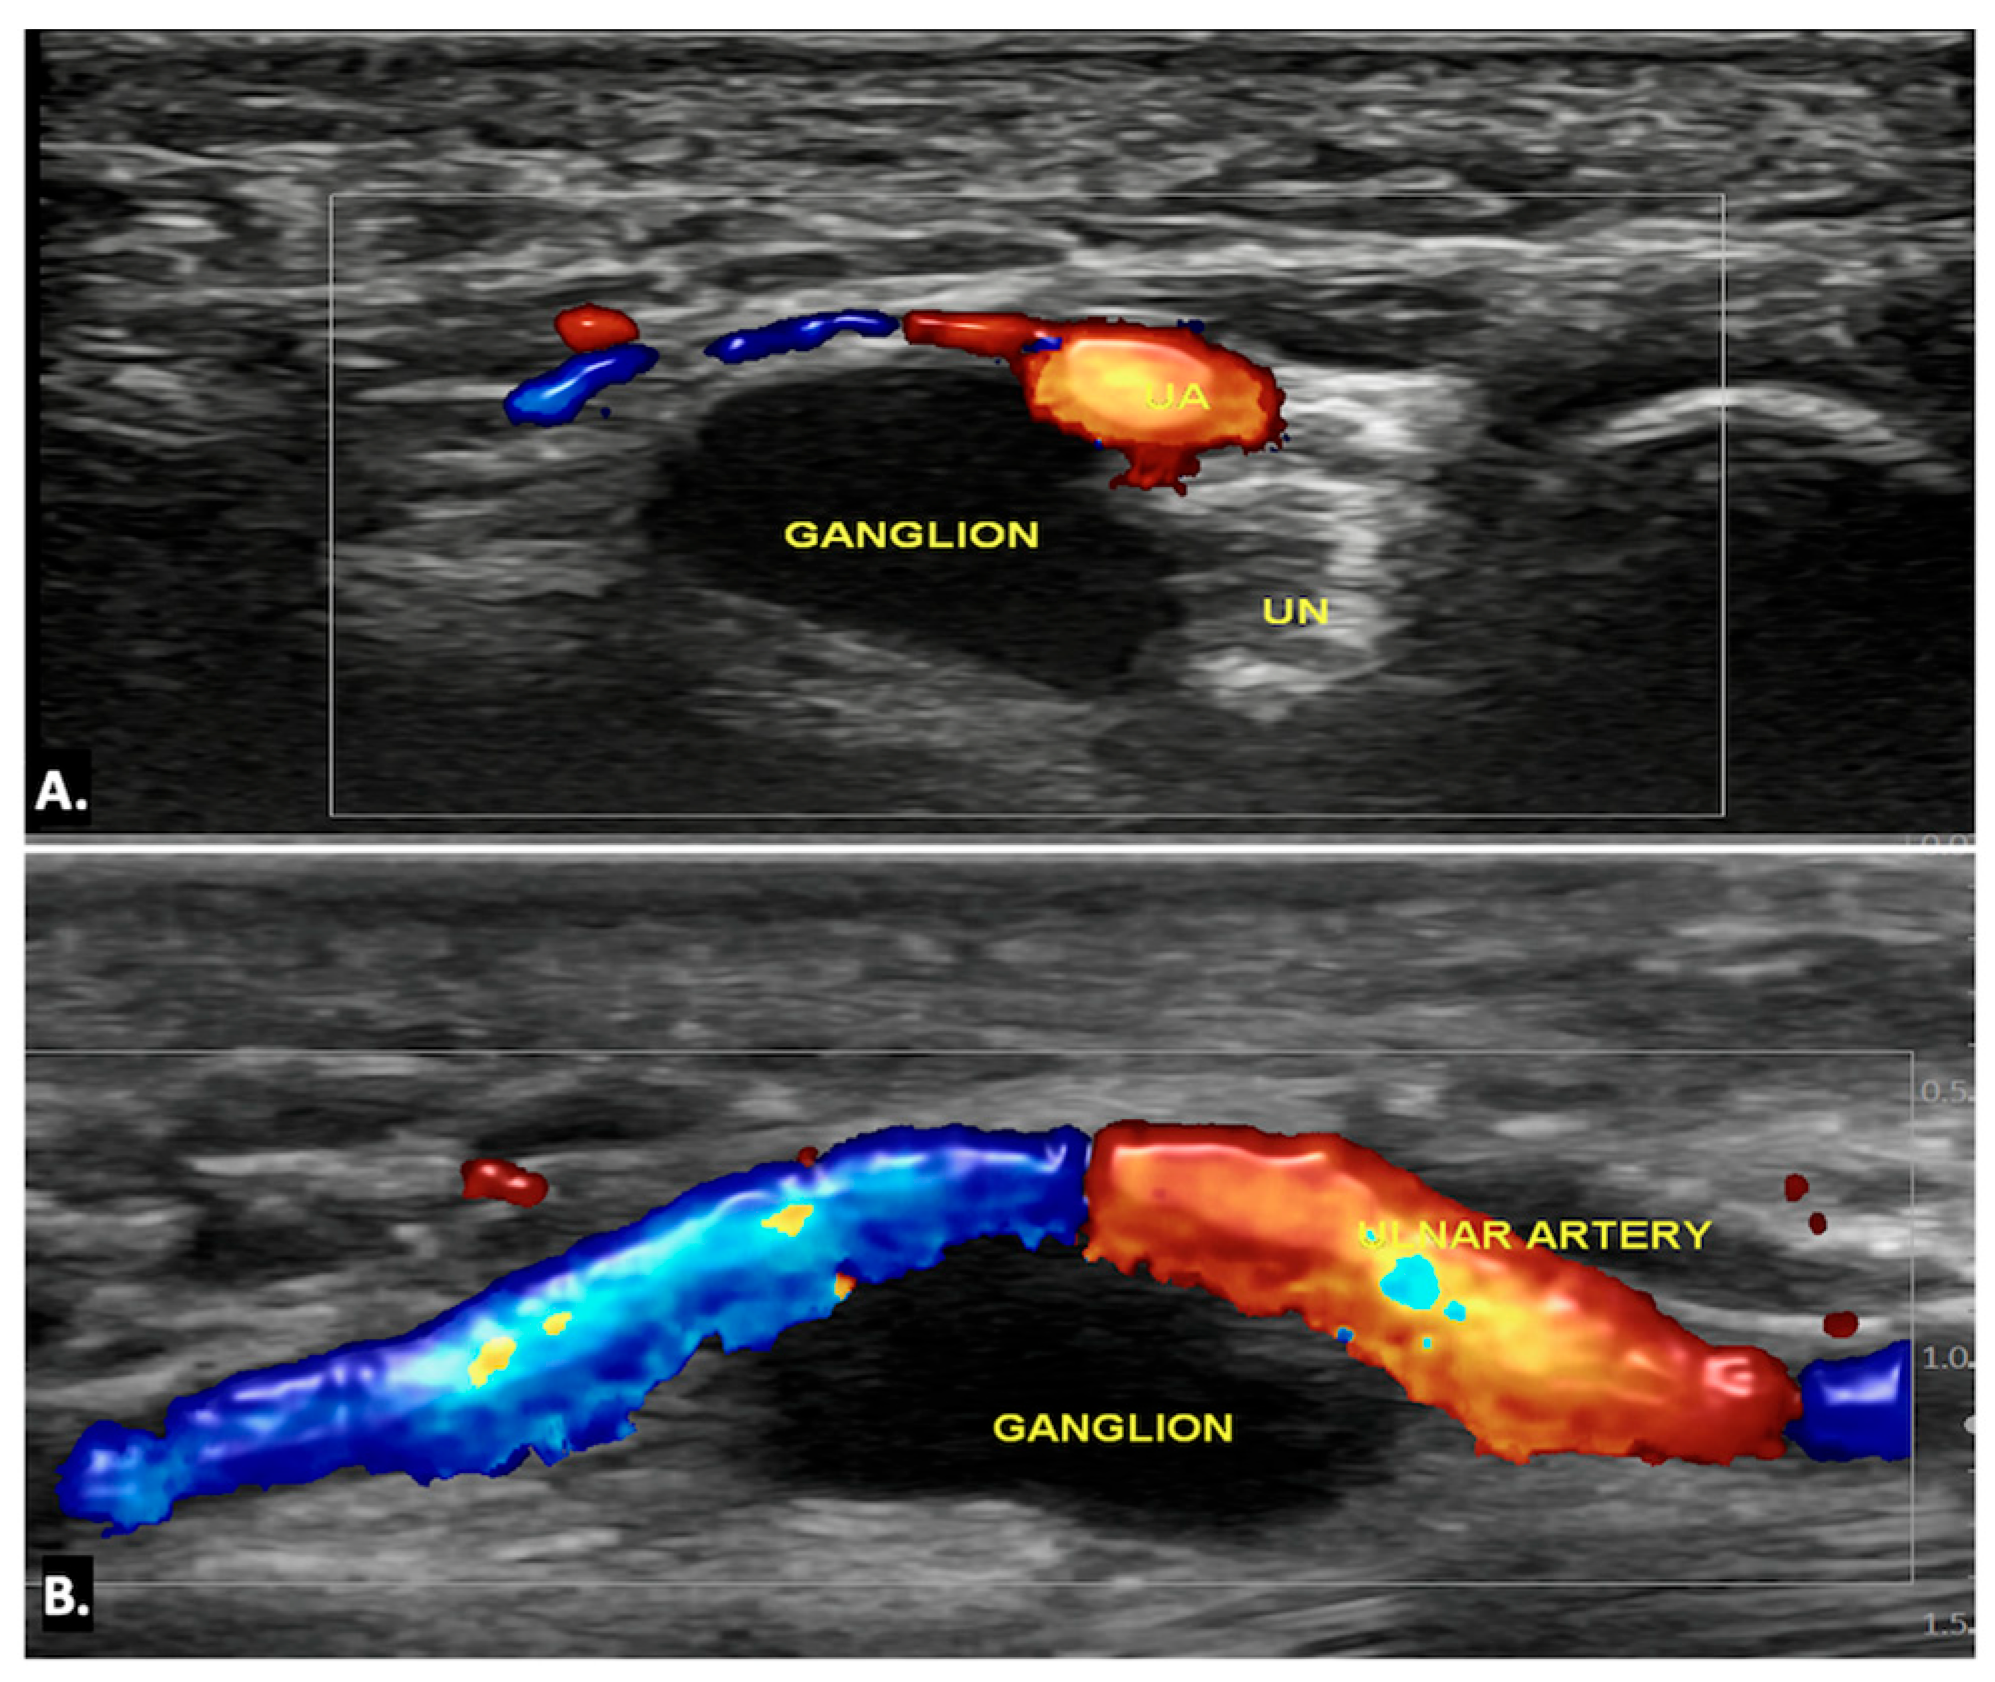

Ultrasound imaging is often the first and typically the only imaging modality required to diagnose a ganglion cyst. On ultrasound imaging, ganglion cysts appear as well-circumscribed anechoic or hypoechoic lesions with posterior acoustic enhancement. They may also show communication with nearby joints or tendon sheaths, which helps confirm their origin. Doppler ultrasound is useful to exclude the possibility of a vascular lesion, such as an aneurysm, by demonstrating an absence of blood flow within the cyst. Additionally, internal signals within the lesion on Doppler may raise suspicion for a sinister aetiology, such as a sarcoma, warranting further investigation (Figure 6) (Video S1) [13,14].

Figure 6.

(A) Axial and (B) longitudinal colour Doppler ultrasound image showing an anechoic cystic lesion within Guyon’s canal, displacing the ulnar artery—likely a simple ganglion cyst.

On MRI, ganglion cysts are well defined, hypointense on T1-weighted images, and hyperintense on T2-weighted images, reflecting their fluid content. Post-contrast images may show thin peripheral enhancement, but the cyst itself does not enhance. Unlike more complex cystic lesions, ganglion cysts usually do not contain calcific foci or haemorrhage. The cyst can cause displacement or compression of the ulnar nerve, which may show an increased signal on T2-weighted images, indicating oedema (Figure 7) [15].